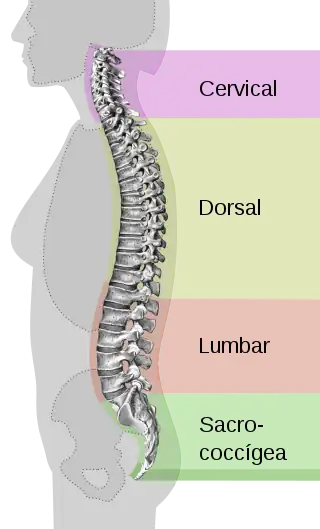

La lordosis fisiológica es un tipo de curvatura fisiológica de convexidad anterior o concavidad posterior, ambas denominaciones son equivalentes. Existen en el cuerpo humano 2 lordosis fisiológicas: cervical, ubicada entre C2 y T1, y lumbar, entre L1 y L5. Estas se pueden observar en la posición de bipedestación desde una vista lateral.[1]

Junto con las dos cifosis fisiológicas, fortalecen la columna vertebral y la protegen de la presión axial, que se produce por ejemplo al caminar; mantiene la posición erguida y ayuda en la prevención de las fracturas axiales.[2] Estas funciones se explican mediante la relación directamente proporcional entre el cuadrado del número de curvas de una columna más uno y la resistencia que ofrece a las fuerzas axiales.[1]

Durante el desarrollo embrionario y durante los primeros 3 meses de vida, el feto no presenta ninguna lordosis, solo presenta una cifosis que abarca toda la columna vertebral. Esta curva se denomina curva simple o primaria. Cuando el lactante logra el control cefálico alrededor de los 3 meses de vida, se desarrolla la lordosis cervical. La lordosis lumbar se desarrolla gradualmente cuando el niño logra sentarse, pararse y caminar. El desarrollo completo de las lordosis normales se da a los 10 años.[2]